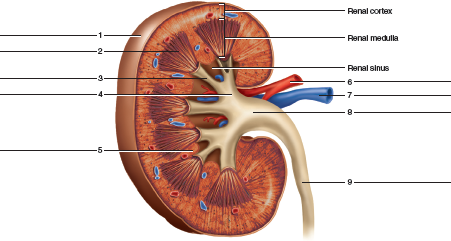

The kidneys are 11 centimeters long paired reddish brown organs situated on the posterior wall of the abdominal cavity one on each side of the vertebral column and capped by the adrenal gland. H ions are produced as a natural byproduct of the metabolism of dietary proteins and accumulate in the blood over time. Connective tissue anchors the kidneys to surrounding structures and helps maintain their normal position.

Upper portions of the kidneys are somewhat protected by the eleventh and twelfth ribs figure 1. Anatomy of the kidneys. Each kidney weighs about 125175 g in males and 115155 g in females.

Due to the presence of the liver the right kidney is slightly lower than the left kidney. They are about 1114 cm in length 6 cm wide and 4 cm thick and are directly covered by a fibrous capsule composed of dense. Anatomy of the urinary system.

The kidneys monitor and regulate the levels of hydrogen ions h and bicarbonate ions in the blood to control blood ph. Glomerular filtration glomerular filtration is the renal process whereby fluid in the blood is filtered across the capillaries of the glomerulus. The right kidney is lower than the left due to displacement by the liver.